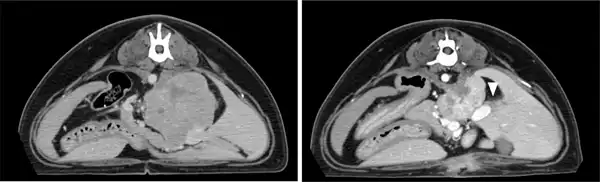

Radiographic and ultrasonographic examinations revealed a mass in the upper abdominal area. Ultrasonography showed that the tumour measured 76 × 51 × 52 mm and had invaded the CVC. The thoracic radiographs ruled out pulmonary metastasis. Following a CT scan (figure 3, left), the tumour was graded as T3N0M0 based on the WHO classification. The radiotherapy regimen included 26 Gy/four fractions/four weeks, and 95 per cent of the tumour received 6.5 Gy. The left kidney over 4 Gy was 31 per cent, and the intestine over 8 Gy was 1.5 ml in one fraction. The first three rounds of radiotherapy followed the same plan, while the fourth one was modified due to a reduction in tumour size. One month after the completion of radiotherapy, a gradual reduction in tumour size was noted. Eighteen months later, the tumour size was reduced to 55 × 37 × 40 mm (figure 3, right), and the tumour volume was down to 40 per cent of the initial volume. There were no radiation toxicities, including changes in renal size, and blood chemistry (before radiotherapy: ALT 28 iu/l, BUN 8.8 mg/dl and Crea 0.5 mg/dl, one month later: ALT 25 iu/l, BUN 15.6 mg/dl and Crea 0.7 mg/dl, two years later: ALT 28 iu/dl, BUN 22.8 mg/dl and Crea 0.6 mg/dl). No adverse events based on VRTOG and VCOG‐CTCAE were detected. However, masses were detected in the spleen, liver and lung after 14, 15 and 17 months, respectively. The spleen mass was resected by the referred veterinary hospital and was diagnosed as a metastatic lesion by haematoxylin and eosin stain histopathology. The dog developed paresis, and the survival time was 25 months after the last radiation therapy.

Figure 3

CT images of the adrenal tumour in case 2. An axial image on day 1 of radiotherapy (left). An axial image at eight months after the initial treatment (right) shows a reduction in the tumour size and changes in the adjacent renal cortex (arrowhead).